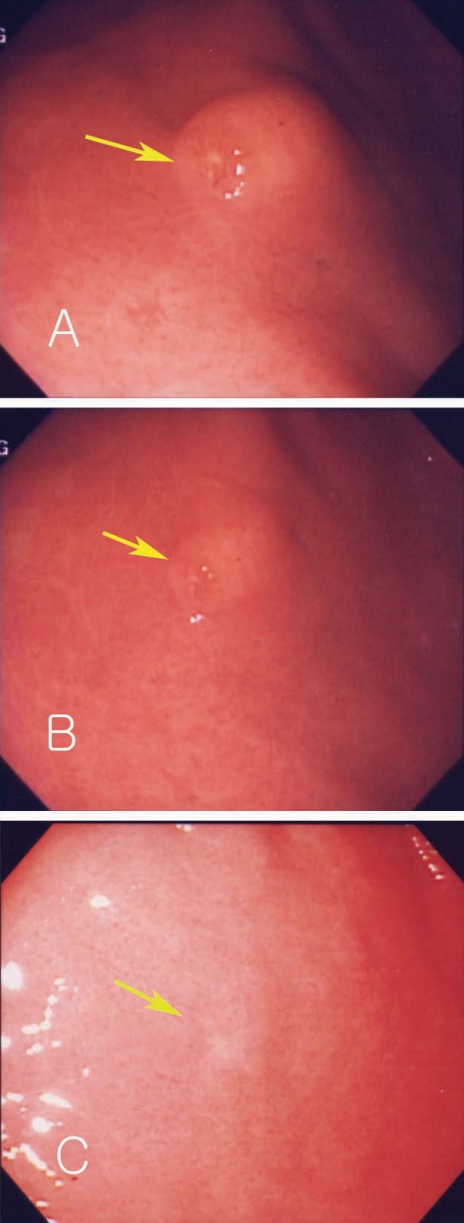

A 45-year-old man complained of abdominal pain and loose stools which had persisted 3 to 4 times a day but without bloody or mucoid diarrhea, fever, or myalgia. His medical history showed no evidence of any specific disease. Physical examination showed stable vital signs. Abdominal epigastric tenderness was presented without rebound tenderness. We prescribed antacids and mucosal protecting agents for conservative management and gastric endoscopy was performed. Endoscopy showed a submucosal tumor-like lesion with yellowish surface at the proximal part of the antrum in the stomach. Some lesions showed erosions and hard surface consistency (Fig. 3A). A biopsy finding revealed severe gastritis with eosinophilic infiltrations. History taking revealed eating of raw sea eels and ascidians before the symptom onset. Laboratory data showed white blood cell count of 13,920 × 103/µL, and eosinophils 12.8%. Considering his history, laboratory test results, and endoscopic and pathologic findings, a submucosal tumor-like lesion caused by anisakid larval infection was suspected. We prescribed albendazole and 2 months later performed a follow-up endoscopy which showed a decrease in size and scarring corresponding to the location of the previous submucosal lesion at the anterior wall of the antrum (Figs. 3B, 3C). A biopsy showed reduced eosinophilic infiltrations and laboratory test showed that white blood cell counts reduced to 7,700 × 103/µL, with eosinophils at 9.6%.